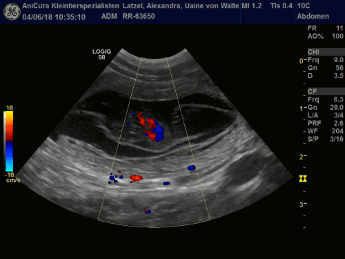

Tessa und Uaine sind schwanger! Die Ultraschallbilder beweisen es! Hier die Bilder!!! |

| Dies sind die Ultraschallbilder von Tessa von Waltenweiler!!! |